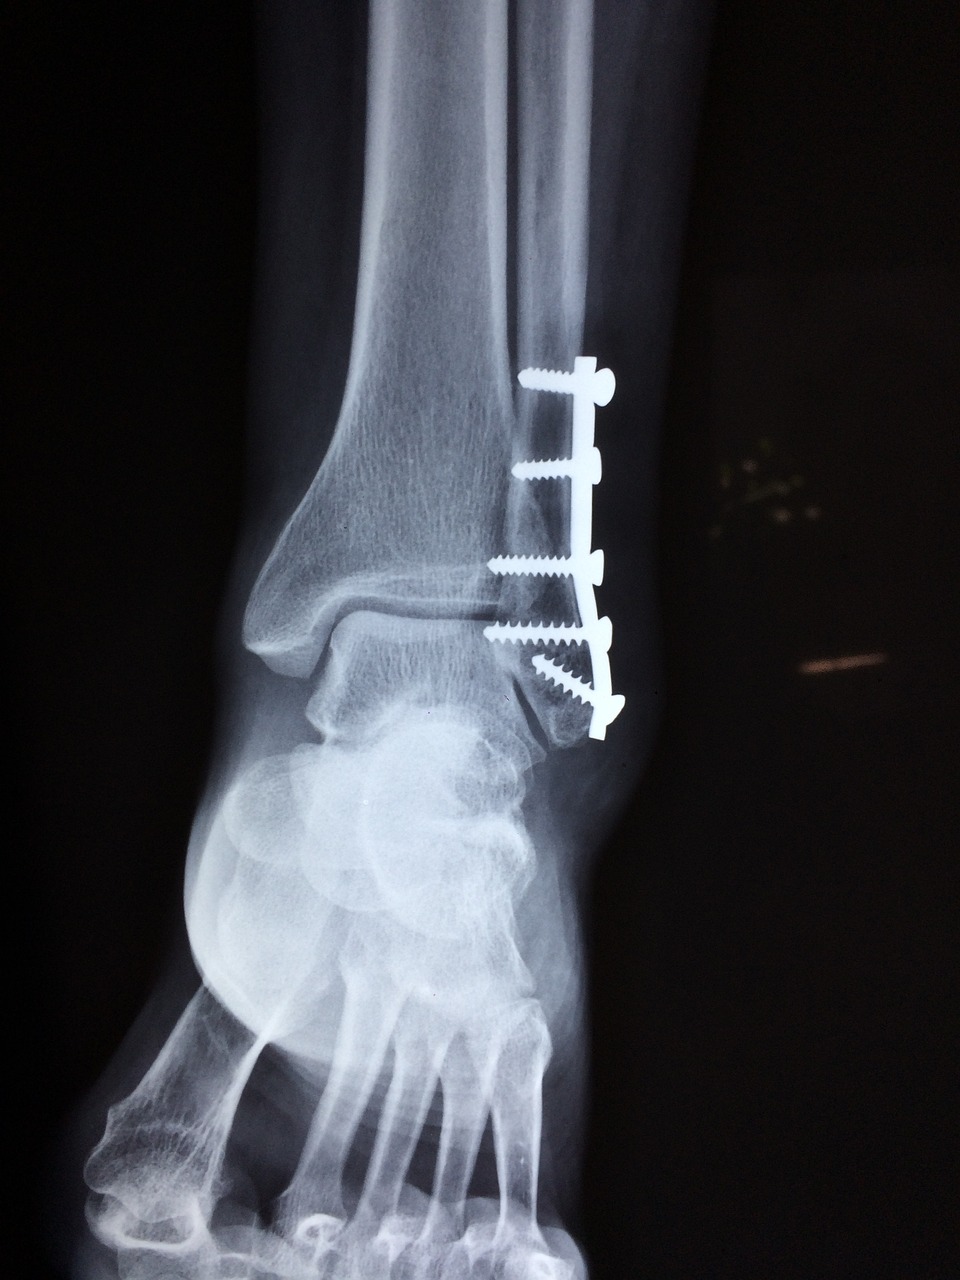

오토바이 사고나 운동 등으로 발 관절에 강한 힘이 가해지면 외과와 내과의 골절과 함께 발관절의 외방 탈구가 일어나게 되는데, 이때 발관절은 강하게 변형되어 부어오르게 되며 대부분은 발관절의 인대 손상등을 동반하게 됩니다.

외과와 내과를 플레이트와 강선등으로 고정시키고, 특히 외과의 정확한 정복과 고정이 중요하며 인대가 끊어졌다면 봉합 수술을 병행할 수 있습니다.